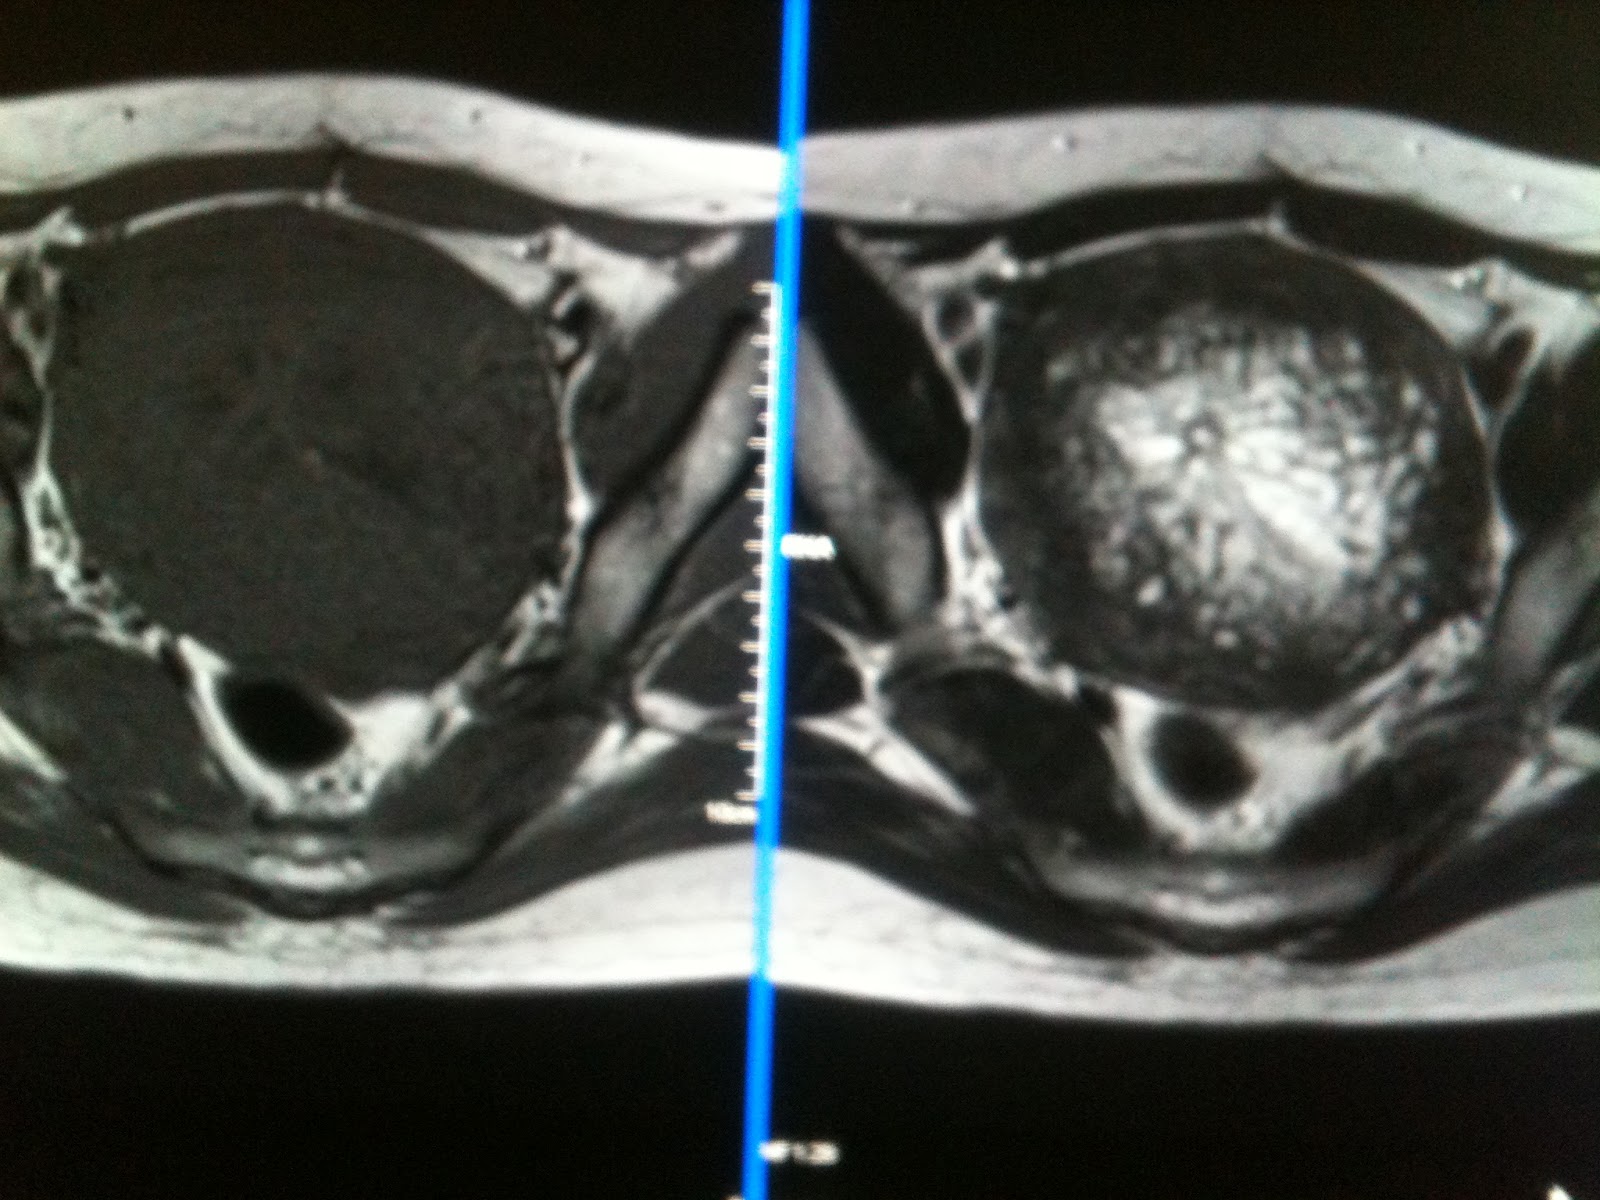

Endometrial Hyperplasia MRI Thickened Endometrium With Cystic Changes usually, there is a homogeneous smooth increase in endometrial thickness, but endometrial hyperplasia may also cause asymmetric/focal. endometrial hyperplasia refers to the thickening of the endometrium. endometrial hyperplasia is a condition where the lining of your uterus is abnormally thick. When your endometrium thickens, it can lead to unusual. The high rate of endometrial hyperplasia in. The. Thickened Endometrium With Cystic Changes.

3Diffuse thickening and cystic change (arrows) of the endometrium in a Thickened Endometrium With Cystic Changes endometrial hyperplasia is a condition where the lining of your uterus is abnormally thick. The high rate of endometrial hyperplasia in. When your endometrium thickens, it can lead to unusual. endometrial hyperplasia refers to the thickening of the endometrium. The appearance, as well as. abnormally thickened endometrium on imaging may occur for a number of reasons which. Thickened Endometrium With Cystic Changes.

Misinterpretation of thickened endometrium On axial contrastenhanced Thickened Endometrium With Cystic Changes This is the layer of cells that line the inside of your uterus. The appearance, as well as. When your endometrium thickens, it can lead to unusual. abnormally thickened endometrium on imaging may occur for a number of reasons which may be categorized based on whether or not they are. cystic endometrium appears to be a powerful predictor. Thickened Endometrium With Cystic Changes.